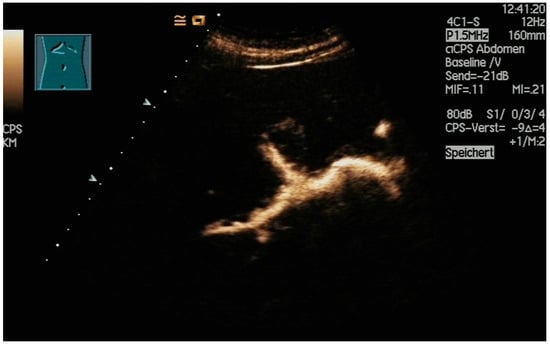

The aims of PGBD are the relief of symptoms and the disappearance of inflammation. If these criteria are met, the drainage can be removed. After pre-existing GB perforation, the integrity of the gallbladder wall should be documented. This can be performed very well by the injection of US-contrast agents (Figure 12 and Figure 13) [80].

Figure 12.

After injection of one drop of SonoVue® diluted in 10 mL sodium chloride 0.9% via drainage, gallbladder perforation and leakage can be excluded. Only the drain and the gall bladder lumen show enhancement (left side: low-MI-mode, right side: conventional grey-scale image).

Figure 13.

Gall bladder perforation. After injection of diluted US-contrast agent via the drain, contrast media appears at the lower liver surface. The drain was left in place for a few more days until surgery could be performed.

After the injection of one drop of SonoVue®, e.g., diluted in 10 mL sodium chloride 0.9% via the drain, gallbladder perforation and leakage can be excluded when only the drainage and the gall bladder lumen show enhancement, and no extravasation is observed.